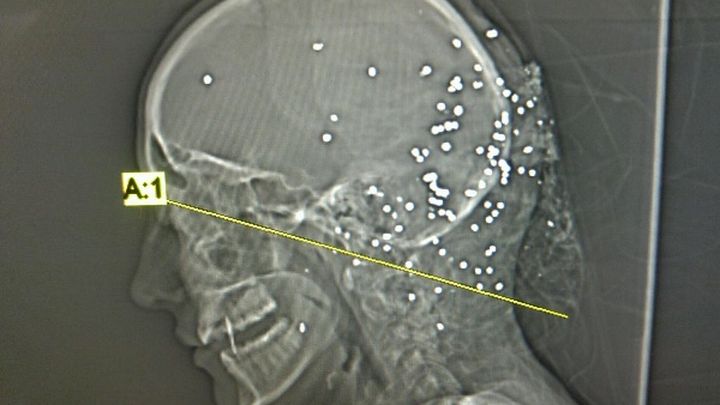

I am trying to raise money for my cousin Lauren who was randomly shot while driving her car. She was shot with bird shot from a shot gun in the side/back of the head. Luckily she is ALIVE! But she has no insurance and is having to see multiple specialists to get the bullets removed from her head and neck. Along with her hospital stay and the specialits she will have to see, all of these medical bills will begin piling up. This was a random act of violence that no one should have to go through! If you can donate anything to help her please do! It will greatly help her through her recovery process